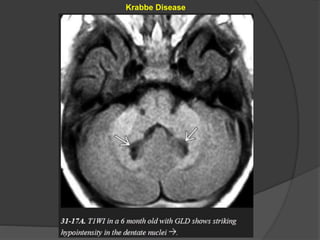

Globoid Cell Leukodystrophy (Krabbe Disease)

GLD is characterized by the presence of unique "globoid" cells in the demyelinating

lesions.

Imaging

NECT scans :

Bilaterally symmetric calcifications

in the thalami, basal ganglia,

internal capsule, corticospinal

tracts, and dentate nuclei of the

cerebellum can sometimes be

Identified.

Classic MR findings in GLD are corticospinal tract hyperintensity on T2/FLAIR

with confluent symmetric demyelination in the deep periventricular WM.

The subcortical U-fibers are typically spared. Bithalamic hypointensity on

T2WI is common.

Diffusion tensor imaging (DTI) may demonstrate reduced fractional anisotropy

in the corticospinal tracts before other abnormalities appear.

MRS findings of elevated choline and decreased NAA in the hemispheric WM

are characteristic but nonspecific.

Cerebellar findings appear early in the disease course.

Alternating "halo" or ring-like hypointensities on T1WI and hyperintensities

on T2WI can be identified in the cerebellar WM surrounding the dentate

nuclei.

Another distinctive feature of GLD is enlargement of the intracranial optic

nerves and chiasm. Diffusely enlarged, enhancing cranial nerves and cauda

equina nerve roots have also been reported in GLD.

Differential Diagnosis

The WM changes in metachromatic leukodystrophy and vanishing white

matter disease may initially appear quite similar, but these disorders lack

the basal ganglia/thalamic calcifications typical of GLD.